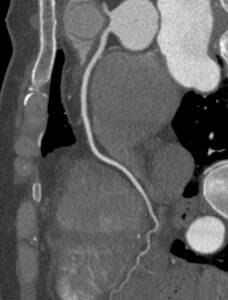

Angiogram

An angiogram is a form of catheter-based diagnostic testing that utilizes an iodine dye to create visible contrast within blood vessels during an X-ray so that vascular and cardiovascular specialists can identify issues and irregularities in the vascular system. The test utilizes a catheter to inject the dye, starting in the femoral artery of the leg, the catheter is steered up the blood vessel via monitor until is in location. This procedure is used to test for blood restrictions and is generally performed when symptoms of coronary artery disease are experienced, such as chest pain (angina), Pain in your chest, jaw, neck or arm that can’t be explained by other tests, new or increasing chest pain (unstable angina), abnormal results on a noninvasive heart stress test, or other blood vessel problems or a chest injury. Like any medical procedure, there are risks, patients with preexisting kidney diseases may not be able to tolerate the iodine dye. Another risk is that the catheter could damage the artery wall or break loose plaque that could travel to the heart, lungs, or brain and cause a stroke. Following the procedure, you should limit certain activity for 3-days or until notified otherwise by your doctor. You should not drive a vehicle or lift items heavier than 10 lbs. You may have tenderness in the incision area